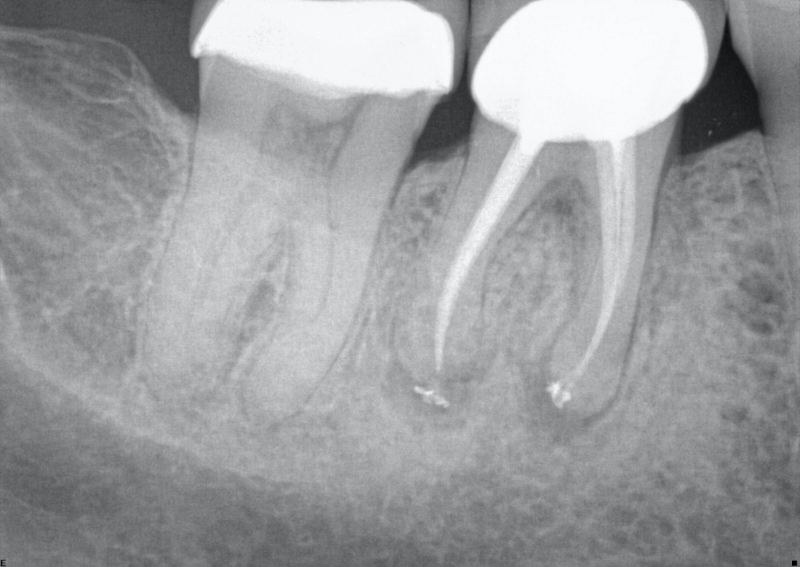

Radiographs and especially CBCT are valuable diagnostic tools for determining the presence of a root fracture. Unfortunately, unless the fracture is wider than about 0.15 mm (the tip of a #15 endodontic file), it cannot be visualized in the CBCT scan. There are some strong associations between radiographic findings and the presence of a root fracture. Specifically, when the bone loss presents in a “J” shaped pattern, it is highly suggestive that a root fracture is present.

This can often be seen on a two-dimensional periapical radiograph, with the bony lesion typically extending from the apex to the crestal bone, sometimes resulting in a deep and narrow isolated periodontal pocket. This pocket sometimes cannot be probed because it occurs in the interproximal area. Taking radiographs of the lower second molars can be challenging, especially with patient compliance (sometimes the tooth is “way back there” and may be uncomfortable for the patient).

Consider this: lower second molars are typically positioned in the cancellous bone, almost directly in the middle of the buccal and lingual cortical bony plates. When pulp necrosis becomes infected, the subsequent bone loss is only observed on a periapical radiograph when the bone loss reaches the junction of the cancellous and cortical bone. This makes the radiographic diagnosis of pulp necrosis difficult, especially for the lower second molar. CBCT can be essential in determining periapical or periradicular bone loss (see Figures 2A-2B).